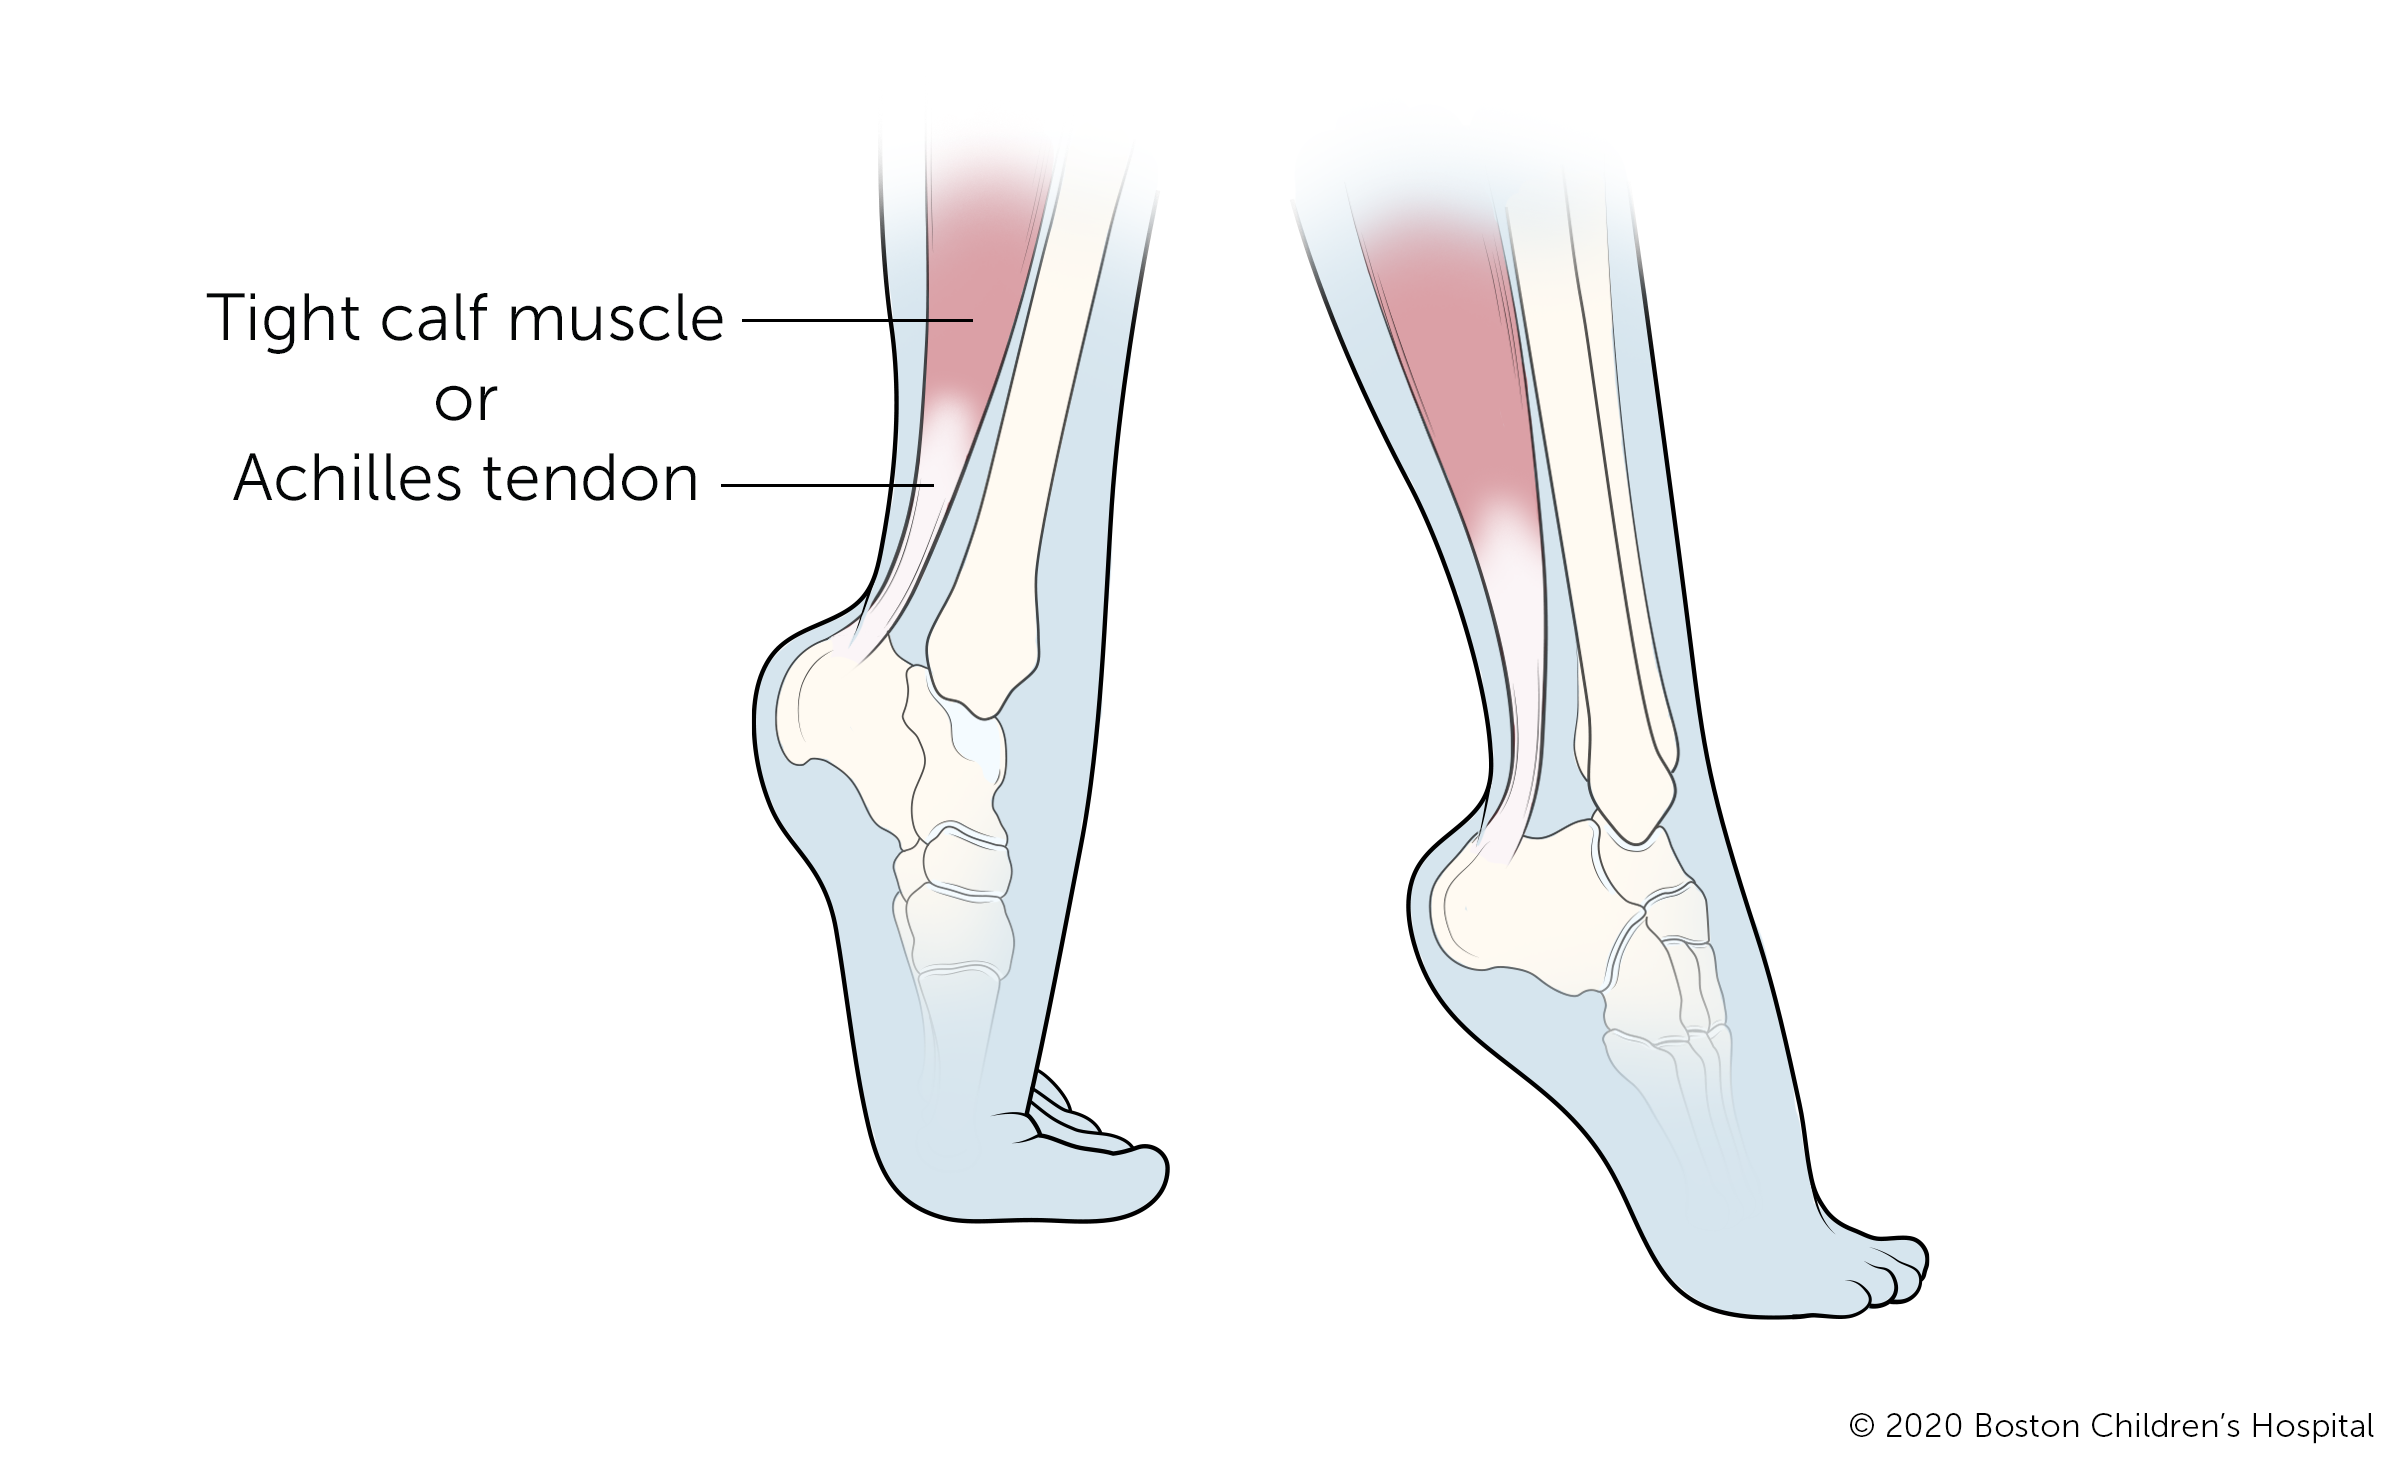

Toe walking

Toe walking is a common gait abnormality, particularly in young children who are just starting to walk. In most cases, this will resolve on its own over time without intervention. However, children who walk normally for a period and then later begin to walk on their toes, or children with tightness of their Achilles tendons, should be evaluated by a physician.

Many cases of persistent toe-walking run in families or are caused by tight muscles. Treatment may involve observation, physical therapy, bracing, casting, or surgery. In some cases, toe-walking may indicate a neuromuscular disorder such as cerebral palsy or it could be a sign of developmental dysplasia of the hip or leg length discrepancy.